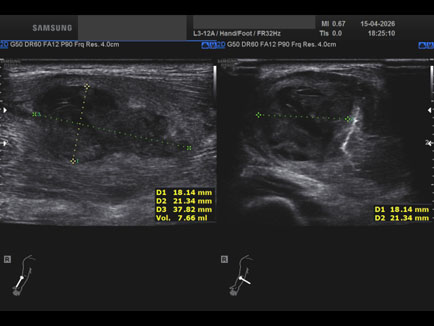

Data inserimento: 17/04/2026

Ecografia del: 15/04/2026

Strumento: Samsung

Sonda: Lineare

Commento all'esame: ematoma post trauma da sforzo del lungo supinatore dx in anziano sottoposto a terapia con i NAO.

Conclusioni: ematoma del muscolo lungo supinatore destro (hematoma of the right supinator longus muscle).